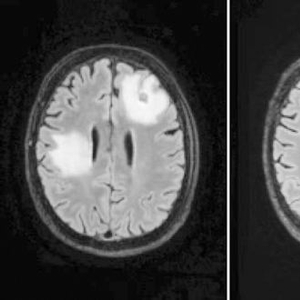

MRI显示,一名脑部感染巴氏阿米巴原虫的男子在接受实验药物治疗前(左)后炎症(白色部分)存在显著差异。

Spottiswoode联系到了DeRisi,但对方表示他们还没有机会使用硝羟喹啉在实际感染者身上进行检验,且该药物没有获得美国食品药品监督管理局的批准。最终,在多方协调下,美国亚虹医药公司为UCSF医疗中心无偿提供了数百粒药片,仅用硝羟喹啉治疗1周后,患者的病变即缩小。随访MRI也显示病情正持续改善,患者现已出院在家中接受后续治疗。近期,第二名患者也开始服用该药物,初步检测结果同样令人鼓舞。(徐锐)